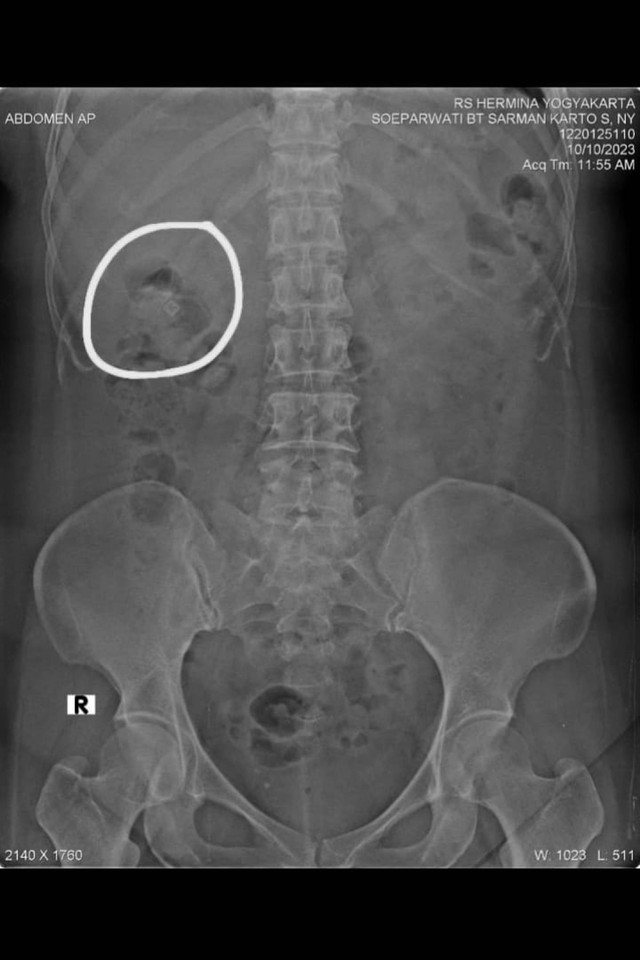

Soeparwati, istri Dosen Fakultas Ilmu Tarbiyah dan Keguruan UIN Sunan Kalijaga Yogyakarta, Dr Zainal Arifin Ahmad, diduga kena sihir atau santet. Paku hingga jarum keluar dari tubuh Soeparwati.

"Beliau menceritakan apa yang dikeluhkan mulai dari paku yang keluar dari muntahan kemudian nyangkut di tenggorokan, kemudian jarum keluar dari pori-pori kulit, habis itu lempengan tembaga yang di usus semuanya terjadi secara misterius," kata Ustaz Faizar melalui sambungan telepon, Selasa (11/6).